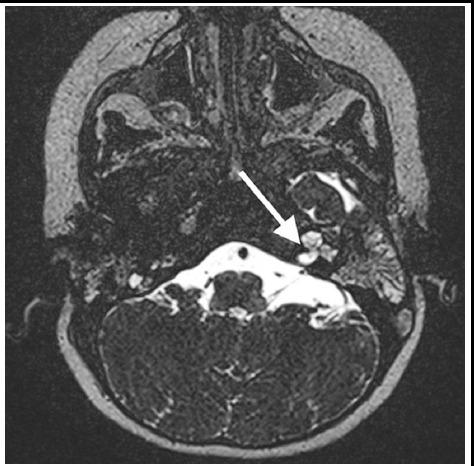

Outcomes of cochlear implantation in children with and without inner ear malformations.

To evaluate the auditory functions and progress of speech development in children with and without cochlear anomalies who underwent cochlear implantation due to prelingual profound sensorineural hearing loss (SNHL).

This study was conducted at Gaziantep University Faculty of Medicine Ear-Nose-Throat Department, between October 2006 and December 2007. A total of 69 children (aged 6 to 24 months) diagnosed with profound SNHL were included. Patients were divided into two groups with respect to the presence of inner ear anomalies: Group-1 consisted of 41 children without inner ear anomaly, whereas Group-2 was composed of 28 patients with inner ear anomalies. The auditory performance was assessed using Listening Progress Profile Test (LPPT) and Monosyllabic Trochee Polysyllabic Test (MTP), the subsections of Evaluation of Auditory Responses to Speech (EARS) test battery.